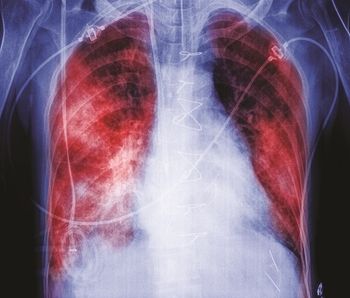

New expert recommendations follow from evidence showing the virus is a thrombo-inflammatory process that can affect multiple organs in addition to the lungs.